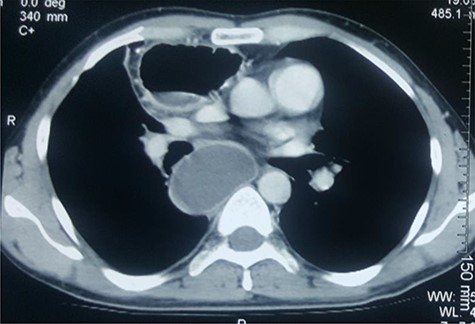

After unremarkable 18 months of the second surgery, he presented with a few days’ history of fever, dysphagia and a painful swelling in the left neck. There was an erythematous, hot cystic swelling measuring 6 cm × 5 cm in the neck underlying the earlier incision. Ultrasound of the neck revealed a loculated collection with some debris, without significant cervical lymphadenopathy. A contrast esophagram was performed which showed an intact esophagogastric continuity without obstruction, stricture, dilatation, leakage or delayed gastric emptying. A CECT scan revealed a distended blind-ended native esophagus filled with high-density fluid extending from neck to the diaphragmatic hiatus (Figs 1 and 2).

CECT of the chest. Note the huge pyocele posteriorly and the gastric conduit anteriorly.